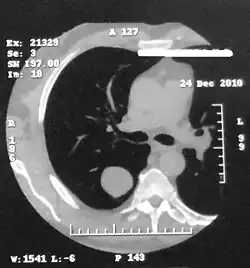

Основным преимуществом компьютерной томографии перед обзорной рентгенографией органов грудной клетки в обследовании пациентов с гамартомой лёгкого является возможность более детальной оценки внутренней архитектуры опухоли благодаря получению тонких срезов. В связи с этим включения кальция и жира лучше визуализируются при компьютерной томографии, чем при рентгенографии[2][10].

При компьютерной томографии органов грудной клетки гамартомы всех гистологических разновидностей дифференцируются в виде объёмного образования овальной формы с чёткими контурами различного диаметра, располагающегося на фоне неизменённой лёгочной ткани без реакции близлежащей междолевой или костальной плевры. Примерно в половине случаев структура гамартомы является неоднородной: либо за счёт центрально расположенных участков обызвествления (в 15—30 %), либо за счёт участков пониженной до −130 HU плотности (жировая ткань, в 34—50 %). Сочетание включений жира и кальция в одной опухоли является характерным признаком гамартомы. Частота обызвествления возрастает с увеличением размеров гамартомы: от 10 % для опухолей менее 2 см до 75 % для гамартом более 5 см[2]. При расположении опухоли в плащевой части лёгкого она имеет подчеркнутые контуры и гладкую поверхность, а при локализации гамартомы в толще лёгочной ткани её удалённый от корня полюс имеет подчёркнутые контуры и гладкую поверхность, обращённый же к корню лёгкого полюс остаётся чётким, но приобретает волнистый характер за счет множества коротких фиброзных тяжей, распространяющихся в ткань лёгкого. Отмечается также характерная ориентация длинной оси гамартомы: при расположении этой опухоли в любом отделе лёгочной ткани её длинная ось всегда направляется в сторону корня лёгкого[3].

При компьютерной томографии с болюсным контрастным усилением изображения отмечается постепенное повышение плотности гамартомы на протяжении всех фаз контрастирования. Характерно, что в артериальную фазу увеличение плотности ткани образования происходит на 57,2 %, в венозную фазу — на 26,4 %[Комм 1][3].